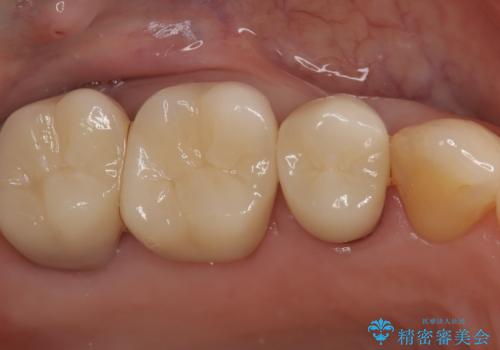

銀歯からセラミックへ。右上奥歯の精密根管治療と審美修復

担当医 河口智英